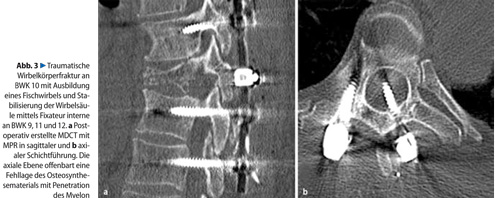

Die postoperative Bildgebung nach chirurgischen Eingriffen muss dem Operateur eine suffiziente Beurteilung des Operationsergebnisses ermöglichen. Insbesondere im Wirbelsäulenbereich ist die Lage des eingebrachten Osteosynthesematerials zu Nachbarstrukturen äußerst wichtig(. Abb. 3). Multiplanare Rekonstruktionendes CT-Primärdatensatzes verschaffen dem Betrachter im Vergleich zu konventionellen Röntgenaufnahmen einen deutlichen Zugewinn an relevanten Informationen, so dass die CT bei dieser Fragestellung das Verfahren der Wahl darstellt.

Metallisches Osteosynthesematerial und Metallimplantate können je nach Zusammensetzung Aufhärtungsartefakte erzeugen und so eine Beurteilbarkeit der angrenzenden Strukturen einschränken. Mittlerweile verbessern jedoch spezifische Rechenalgorithmen zur Unterdrückung von Metallartefakten die Bildqualität signifikant. Die Beurteilung der spinalen Weichgewebsstrukturen inklusive des Bandapparates, des Myelons sowie der Nachweis okkulter und belastungsbedingter (Stress-)Frakturen bleibt auch in der posttraumatischen Bildgebung eine Domäne der MRT.